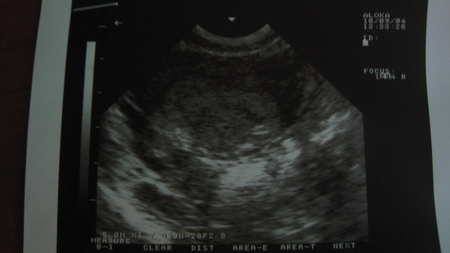

приветик,сегодня былы на узи! сегодня 11 день задержки!она сказала что плодного яйца нет! но говорит какае то перегородка(странно),ещё странно что сегодня сделала с утра 2 тестика один показал более сильнуу полосочку, второй слабенькую полосочку! как то это всё странно! хлотела ещё спрость,мне врачь сказал что у меня матка седловидная, это плохо??

вот что написали: тело матки: продольный 40,передне-задний 29,поперечный 34, эндометрий-10 мм. ПЯ-32*17*12, ЛЯ-25*23*20 с фолик 5,6 мм